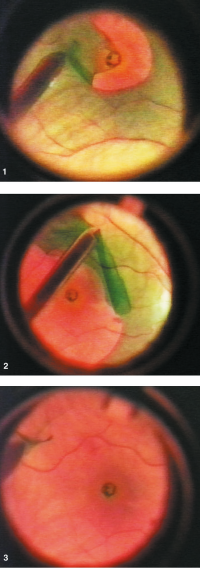

Indocyanine green (ICG) is a green anionic cyanine dye that is useful for ILM staining. It has high affinity for components of the extracellular matrix present in the ILM such as collagen type IV and laminin. In porcine studies, ICG causes increased stiffness of the ILM when it is exposed to light, possibly due to alterations in collagen structure.[22] This stiffening may facilitate easier removal in one piece with less damage to underlying tissues. Various studies have shown improved ease of ILM removal and less trauma when ICG is applied before ILM peeling.[23] ICG requires initial dilution in distilled water. If diluted initially in saline, the dye can precipitate. The diluted solution should then be subsequently diluted in balanced saline solution to create a less hypo-osmolar solution.

There are some concerns over ICG’s toxicity when used intraocularly. A meta-analysis of 837 eyes showed similar anatomical outcomes when using ICG versus no dye in ILM peels, but worse functional outcomes.[24] The authors implicated dye-induced toxicity as a possible culprit. Numerous animal studies have shown that ICG is toxic to chorioretinal cells when exposed to moderate to high concentrations. ICG has also been proposed to cause toxicity when applied and exposed to light through a photochemical mechanism. Studies performed in rabbits resulted in RPE changes and functional retinal damage when subretinal ICG injections were exposed to light.[25][26] The FDA has approved ICG for intravenous use in angiography, but not for intraocular use. Thus, its use in vitreoretinal surgery is currently off-label.